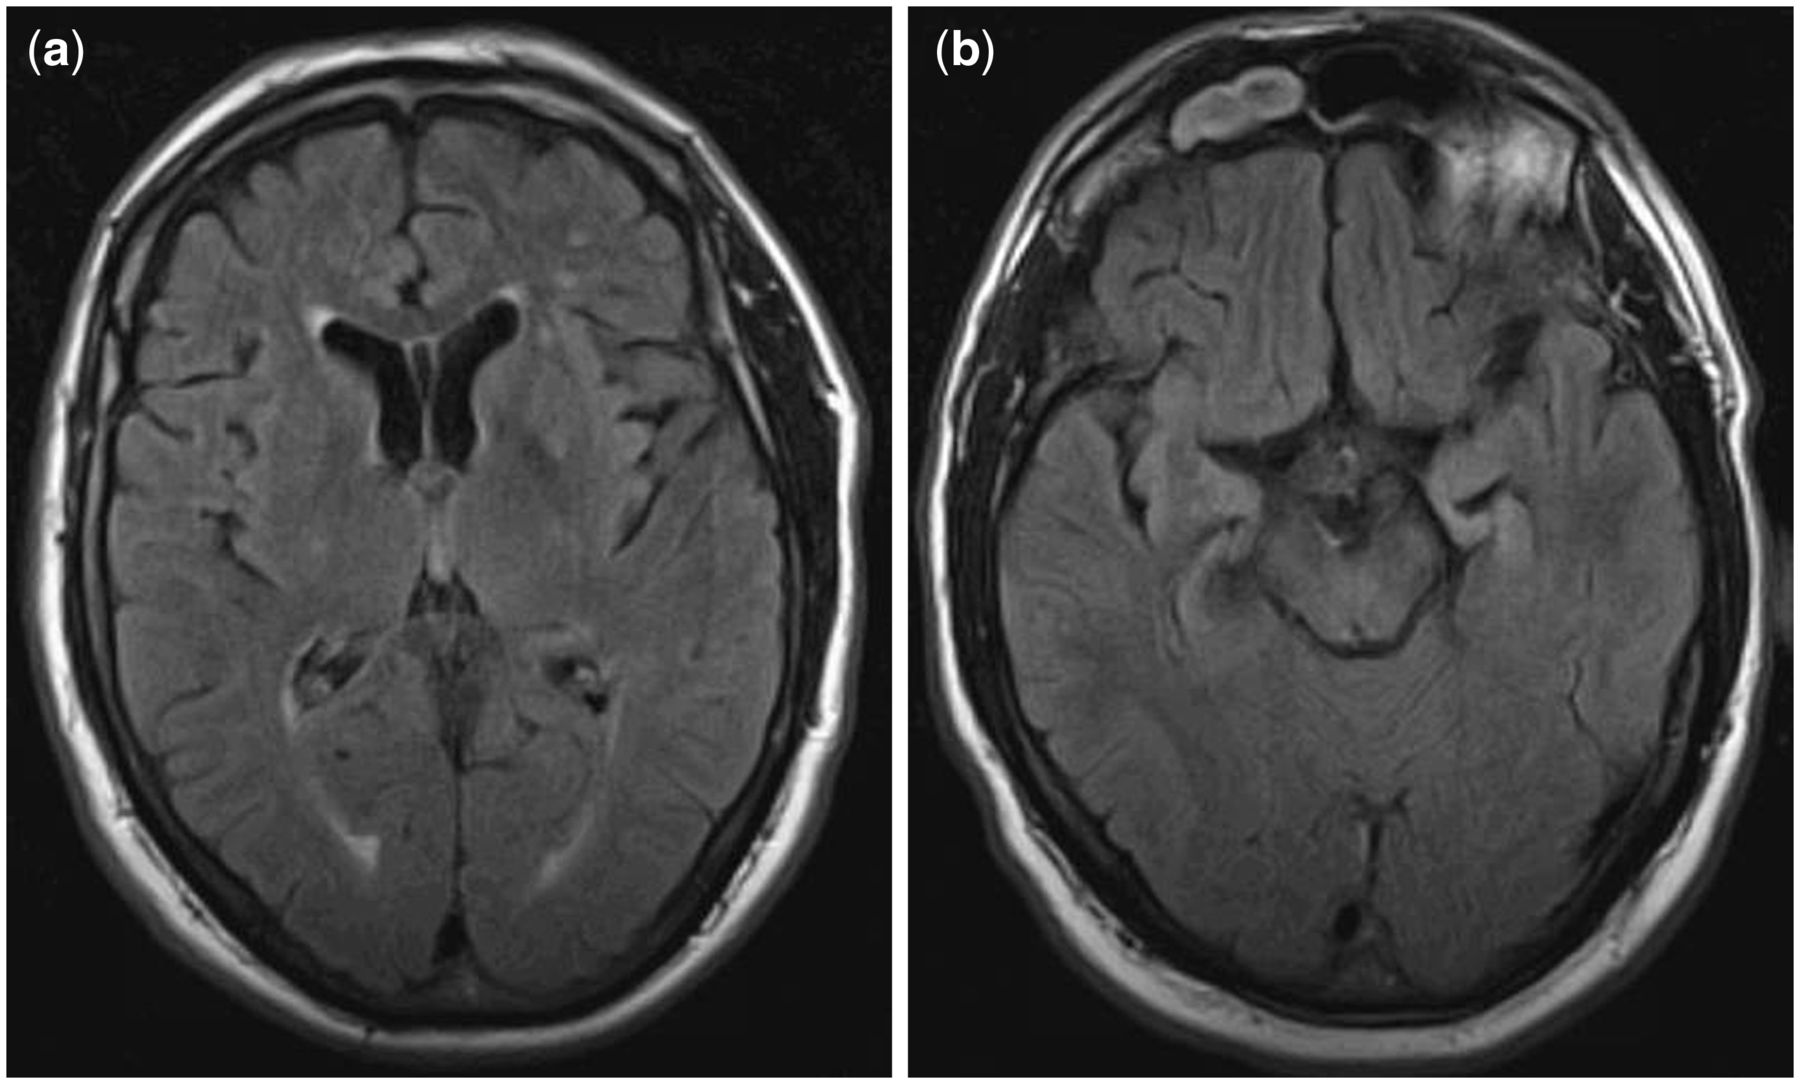

Хроническая Травматическая Энцефалопатия